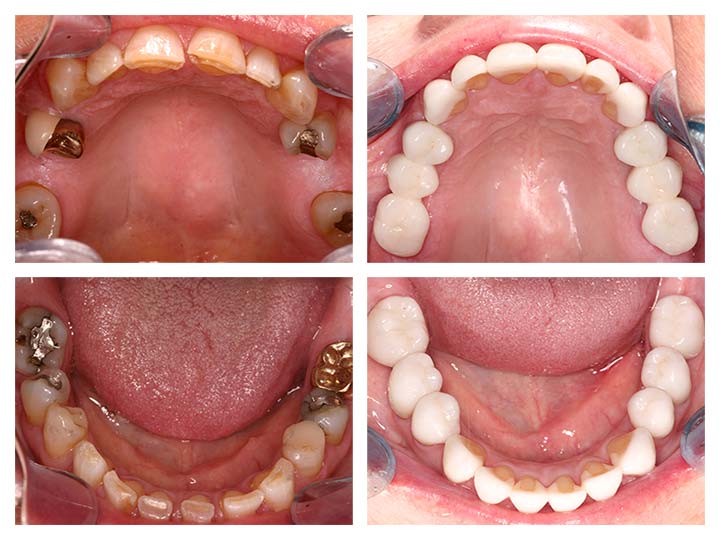

Before And After Bridges and Crowns Treatment